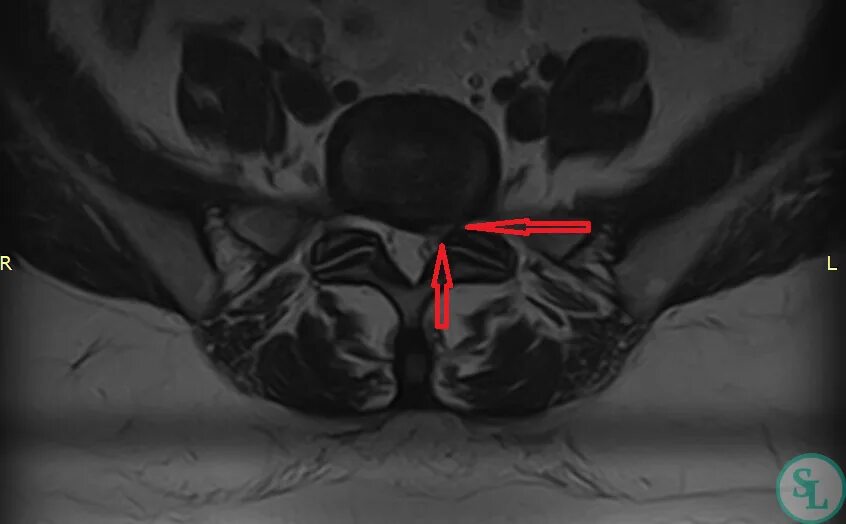

Грыжа диска l5 лечение